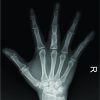

A 56-year-old female patient presented to our clinic for left hand middle finger edema and pain of 1-year duration. Her medical history was relevant for 15 years of progressive 4th and 5th fingers malformations that were attributed to sarcoidosis, and for which she was treated with anti-inflammatory and low dose steroids therapy; she stated that the malformation started in the form of pain and edema 15 years before achieving this neglected form. One year before presentation, the patient started noticing left middle finger edema and swelling associated with severe pain and a mass-like structure over the 1st phalanx. This was preceded by few days of weakness and fatigue. She sought medical advice at multiple clinics where the new mass was first diagnosed as bone cancer. At our clinic, physical examination was consistent with a swelling at the base of the middle finger (Fig. 1) associated with tenderness and decreased range of motion. Laboratory tests were within normal limits, except for elevated C-reactive protein, and erythrocyte sedimentation rate. Purified protein derivative test was negative. Radiographs of the hand showed a lytic lesion involving the distal half of the first phalanx, along with blurred limits of the bone surfaces involved (Fig. 2). An magnetic resonance imaging was ordered and showed hyper-intense signal of the first phalanx, along with subcutaneous enclosed collections on both sides of the phalanx (Fig. 3).

Then, an osteotomy was done at the distal metaphyseal region of the first phalanx, followed by debridement of the diaphyseal marrow (Fig. 4) that was sent for pathology. The osteotomy was reduced and fixed using 2 k-wires. Post-operative radiographs are shown in Fig. 5.